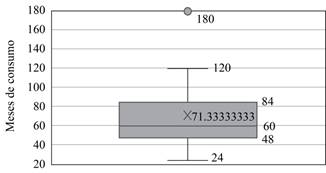

El consumo de bifosfonatos se observó en 80.6% de pacientes con FAF y en 3.57% con FS/FD. El tiempo de consumo de BF fue determinado en 15 de los 25 pacientes con FAF y fue desde 24 hasta 180 meses, con media de 71.3 meses; 75% de estos pacientes tuvo un consumo de 48 meses o más (Figura 6).

Existió relación directa entre el uso prolongado de BF y el desarrollo de FAF, se demostró que este tipo de fracturas se presentaron en personas con uso mayor a dos años; con mayor número de casos conforme aumenta el tiempo de consumo, similar a lo reportado en otros estudios.9,11,25